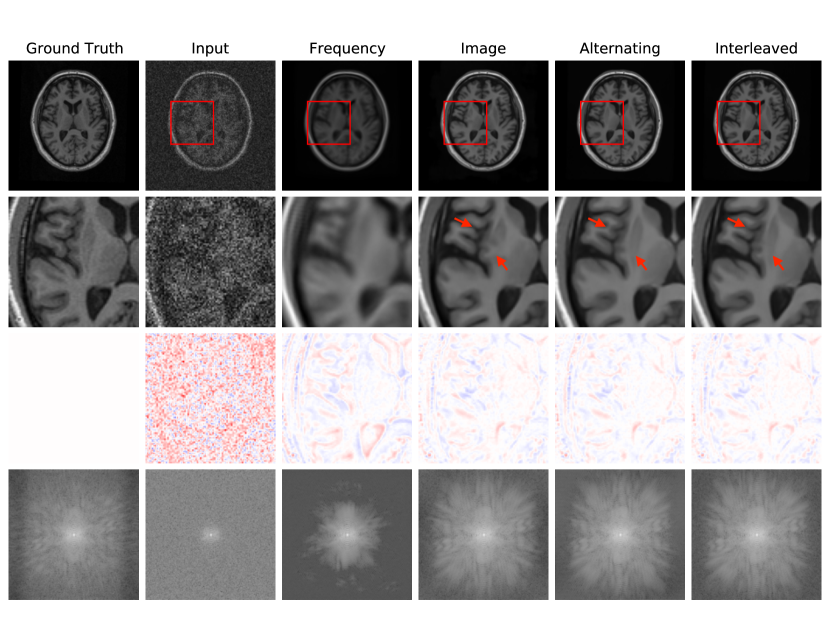

Fig. 4 reports reconstruction quality statistics for all four types of simulations described in Section 4.1.1: motion, noise, undersampling, and motion combined with undersampling. The Interleaved and Alternating architectures outperform the baseline architectures for nearly every task and subject. Across all tasks and nearly all subjects, the Interleaved and Alternating architectures are quite similar in numerical performance. Sample image reconstructions for the motion, motion with undersampling and denoising tasks are shown in Figs. 5-7. Qualitatively, for each task, the Frequency network provides a blurry version of the ground truth image. The Image network provides a reconstruction which effectively removes ‘background’ effects but has limited success in correcting these artifacts within the image. In contrast, the Interleaved and Alternating networks provide sharper, high-quality reconstructions across all tasks. Further, the frequency space reconstructions provided by those networks appear the most faithful to the ground truth frequency data.